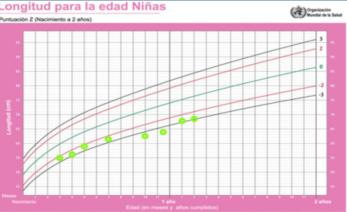

El crecimiento en peso, longitud y perímetro craneano según la edad se muestran en las (Figura 1), (Figura 2) y (Figura 3). En la (Figura 4) se muestra la evolución del peso de acuerdo a la longitud.

Figura 2: Gráfica de la longitud para la edad. Los puntos verdes indican los valores para esta paciente de acuerdo a la edad

La antropometría en el momento de la consulta evidenció: peso de 8 kg (score Z del índice antropométrico peso para la edad -1,7); longitud de 68 cm (score Z de longitud para la edad -3,3). La relación peso/longitud tenía un score Z de 0,27. El perímetro cefálico era de 47 cm (score Z 0,55).

Esta niña presentaba una talla baja, por tener una longitud para la edad con un puntaje Z o desvío estándar (DE) menor a -2. Se trataba de una talla baja severa, por estar este índice antropométrico por debajo de -3 DE. Se realizó la medida de los segmentos corporales. El segmento superior (SS), medido desde la sínfisis pubiana hasta el suelo5, fue de 44 cm. El segmento inferior (SI) que se obtuvo restando el SS a la talla fue de 24 cm. En esta paciente la relación SS/SI fue de 1,83, siendo el valor normal para la edad menor a 1,7. Se confirmó de esta forma que se trataba de una talla baja desproporcionada.

En los primeros dos años de vida se alcanza el carril de crecimiento que corresponde a la carga genética. Posteriormente y hasta el inicio del desarrollo puberal, no es habitual cambiar de carril de crecimiento. Si esto sucede, amerita una evaluación exhaustiva. Luego de los 2 años no debieran producirse cambios en la curva de crecimiento mayores a 0,25 DE/año9. Los niños pequeños para la edad gestacional pueden ser una excepción a esta afirmación2,5,13. En el caso presentado se evidenció una desaceleración del crecimiento desde el sexto mes de vida.